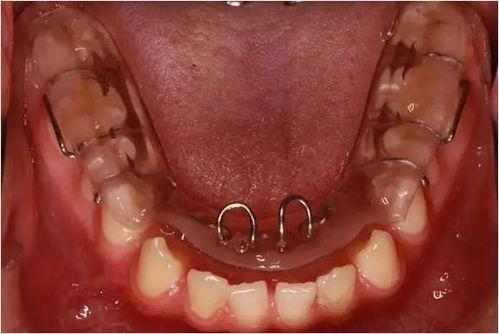

舌側(cè)固定保持器

舌側(cè)固定保持器是將一根細(xì)細(xì)的鋼絲用特殊的粘結(jié)劑粘在牙齒的舌側(cè)面,固定在牙齒上,無需摘戴。

優(yōu)點(diǎn):固定在牙齒內(nèi)側(cè),完全隱形,不影響美觀和日常生活;保持效果穩(wěn)定。

缺點(diǎn):不易清潔,需要特別注意口腔衛(wèi)生;如果有個(gè)別牙齒出現(xiàn)問題,調(diào)整較為困難。